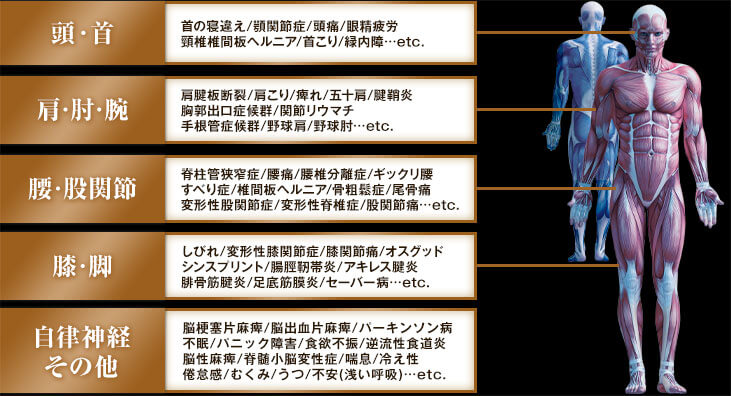

| 頭・首 | 首の寝違え 顎関節症 頭痛 眼精疲労 頸椎椎間板ヘルニア 首こり 緑内障…etc. |

|---|---|

| 肩・肘・腕 | 肩腱板断裂 肩こり 痺れ 五十肩 腱鞘炎 胸郭出口症候群 関節リウマチ 手根管症候群 野球肩 野球肘…etc. |

| 腰・股関節 | 脊柱管狭窄症 腰痛 腰椎分離症 ギックリ腰 すべり症 骨粗鬆症 椎間板ヘルニア 尾骨痛 変形性股関節症 変形性脊椎症 股関節痛…etc. |

| 膝・脚 | しびれ 変形性膝関節症 膝関節痛 オスグッド シンスプリント 腸脛靭帯炎 アキレス腱炎 腓骨筋腱炎 足底筋膜炎 セーバー病…etc. |

| 自律神経 その他 |

脳梗塞片麻痺 脳出血片麻痺 パーキンソン病 不眠 パニック障害 食欲不振 逆流性食道炎 脳性麻痺 脊髄小脳変性症 喘息 冷え性 倦怠感 むくみ うつ 不安(浅い呼吸)…etc. |